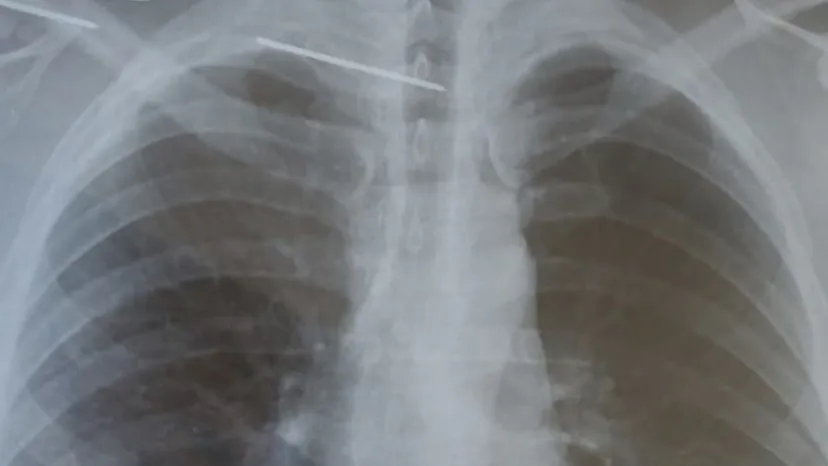

Хирургам Рязанской ОКБ удалось вытащить из позвоночника рязанца металлическую спицу, пишет Издательство "Пресса". По словам главврача больницы Андрея Карпунина, спица прошла через сосудистый нервный пучок, пересекла грудной отдел позвоночника и проткнула спинной мозг. Это привело к снижению чувствительности ног пациента.

Выяснилось, что ранее в одной из клиник металлической спицей скрепили ключицу пациента. По неизвестной причине спица отлоколась от кости и проникла в позвоночник, вызвав еще и гнойно-септическое осложнение.